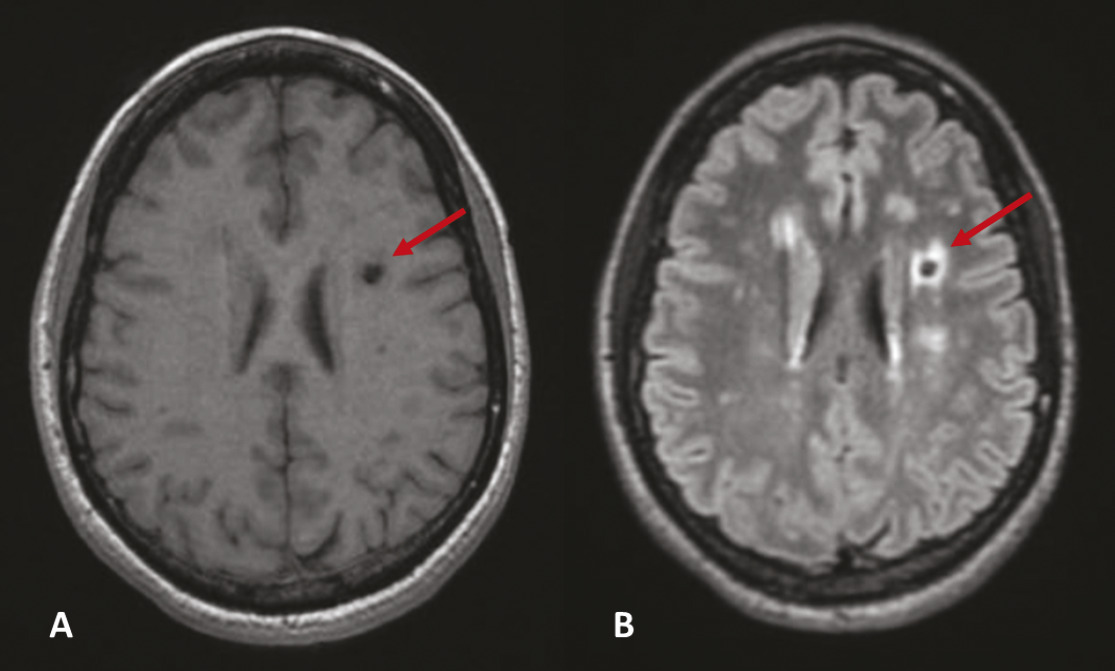

Lacunes, stigmates de lésions anciennes

Les lacunes sont des « trous » ovoïdes sous-corticaux, de 3 à 15 mm de diamètre, correspondant à une ancienne petite lésion ischémique ou hémorragique profonde dans le territoire d’une artère perforante, remplie de liquide céphalo­rachidien. La traduction à l’IRM cérébrale est une lésion en hyposignal T1 et T2, pouvant être entourée d’une couronne hyper­intense en T2 FLAIR (fig. 2). Si la taille le permet, il est possible de voir une hypodensité au scanner.5